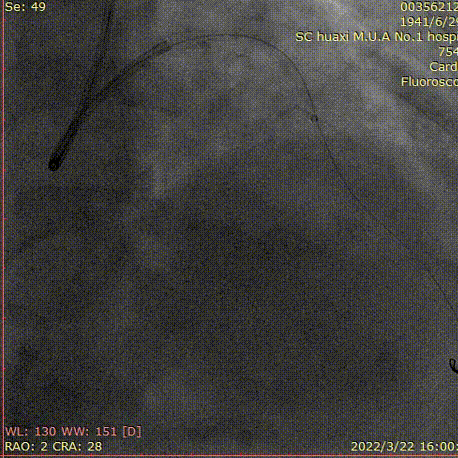

说明:IVUS确定真腔入口,XTA导丝进入,Pilot200,CP穿刺,仍在假腔。

说明:多体位确定导丝与真腔的关系,2.0球囊扩张近段,交换为ADR球囊。

说明:CP穿刺成功,交换为工作导丝,2.5球囊扩张前降支。